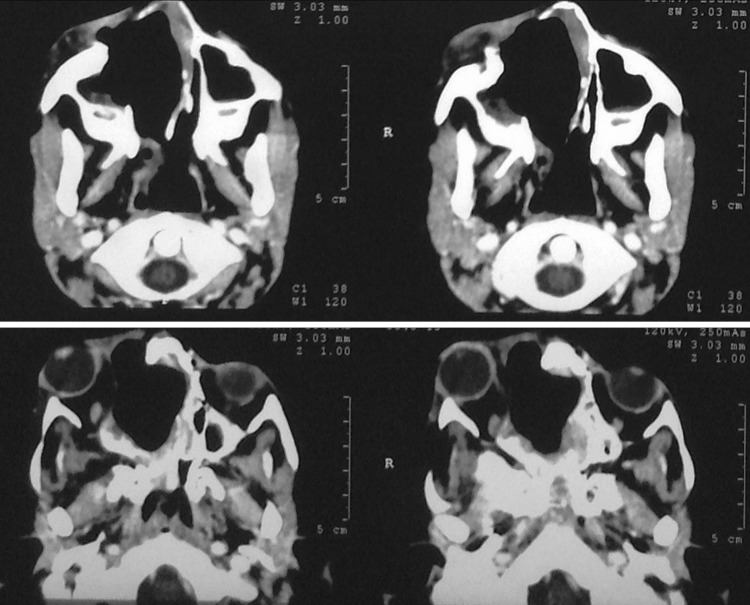

| CECT | |||

| A heterogeneously enhancing well defined mass of the paranasal sinus causing bony remodeling of all the walls with thinned out cortical bone. Areas of new bone formation seen dispersed within the lesion | Lesion occupying the entire maxillary sinus with thinned out anterolateral and posterolateral walls, causing bulge in the floor of orbit, lateral nasal wall and right half of hard palate. Cortical bone erosion in right malar region | Lesion involving B/L posterior ethmoids, right anterior ethmoids and middle meatus and sphenoid sinus with thinning of B/L lamina papyracea. Intracranial, extradural extension through the planum sphenoidale | Lesion involving B/L posterior ethmoids extending to right pterygopalatine fossa and posterior choana, sphenoid sinus with intracranial, extradural involvement in suprasellar and prepontine cisterns. Right parasellar extension encasing the right internal carotid artery and extension into B/L optic canal present |

| MRI with contrast | |||

| A heterogeneously enhancing iso to hypointense mass, either completely solid or with cystic spaces. Areas of internal septatations present. No evidence of frank intradural, intraorbital or infratemporal fossa extension | |||

Representative Radiology (Figs. 1, 2, 3, 4)